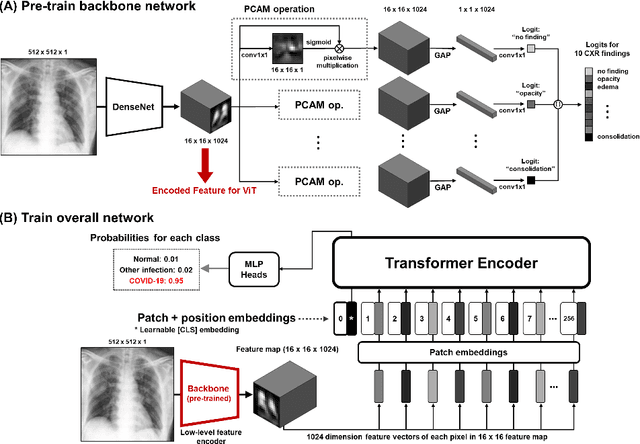

Abstract:Developing a robust algorithm to diagnose and quantify the severity of COVID-19 using Chest X-ray (CXR) requires a large number of well-curated COVID-19 datasets, which is difficult to collect under the global COVID-19 pandemic. On the other hand, CXR data with other findings are abundant. This situation is ideally suited for the Vision Transformer (ViT) architecture, where a lot of unlabeled data can be used through structural modeling by the self-attention mechanism. However, the use of existing ViT is not optimal, since feature embedding through direct patch flattening or ResNet backbone in the standard ViT is not intended for CXR. To address this problem, here we propose a novel Vision Transformer that utilizes low-level CXR feature corpus obtained from a backbone network that extracts common CXR findings. Specifically, the backbone network is first trained with large public datasets to detect common abnormal findings such as consolidation, opacity, edema, etc. Then, the embedded features from the backbone network are used as corpora for a Transformer model for the diagnosis and the severity quantification of COVID-19. We evaluate our model on various external test datasets from totally different institutions to evaluate the generalization capability. The experimental results confirm that our model can achieve the state-of-the-art performance in both diagnosis and severity quantification tasks with superior generalization capability, which are sine qua non of widespread deployment.

Vision Transformer for COVID-19 CXR Diagnosis using Chest X-ray Feature Corpus

Abstract:Under the global COVID-19 crisis, developing robust diagnosis algorithm for COVID-19 using CXR is hampered by the lack of the well-curated COVID-19 data set, although CXR data with other disease are abundant. This situation is suitable for vision transformer architecture that can exploit the abundant unlabeled data using pre-training. However, the direct use of existing vision transformer that uses the corpus generated by the ResNet is not optimal for correct feature embedding. To mitigate this problem, we propose a novel vision Transformer by using the low-level CXR feature corpus that are obtained to extract the abnormal CXR features. Specifically, the backbone network is trained using large public datasets to obtain the abnormal features in routine diagnosis such as consolidation, glass-grass opacity (GGO), etc. Then, the embedded features from the backbone network are used as corpus for vision transformer training. We examine our model on various external test datasets acquired from totally different institutions to assess the generalization ability. Our experiments demonstrate that our method achieved the state-of-art performance and has better generalization capability, which are crucial for a widespread deployment.